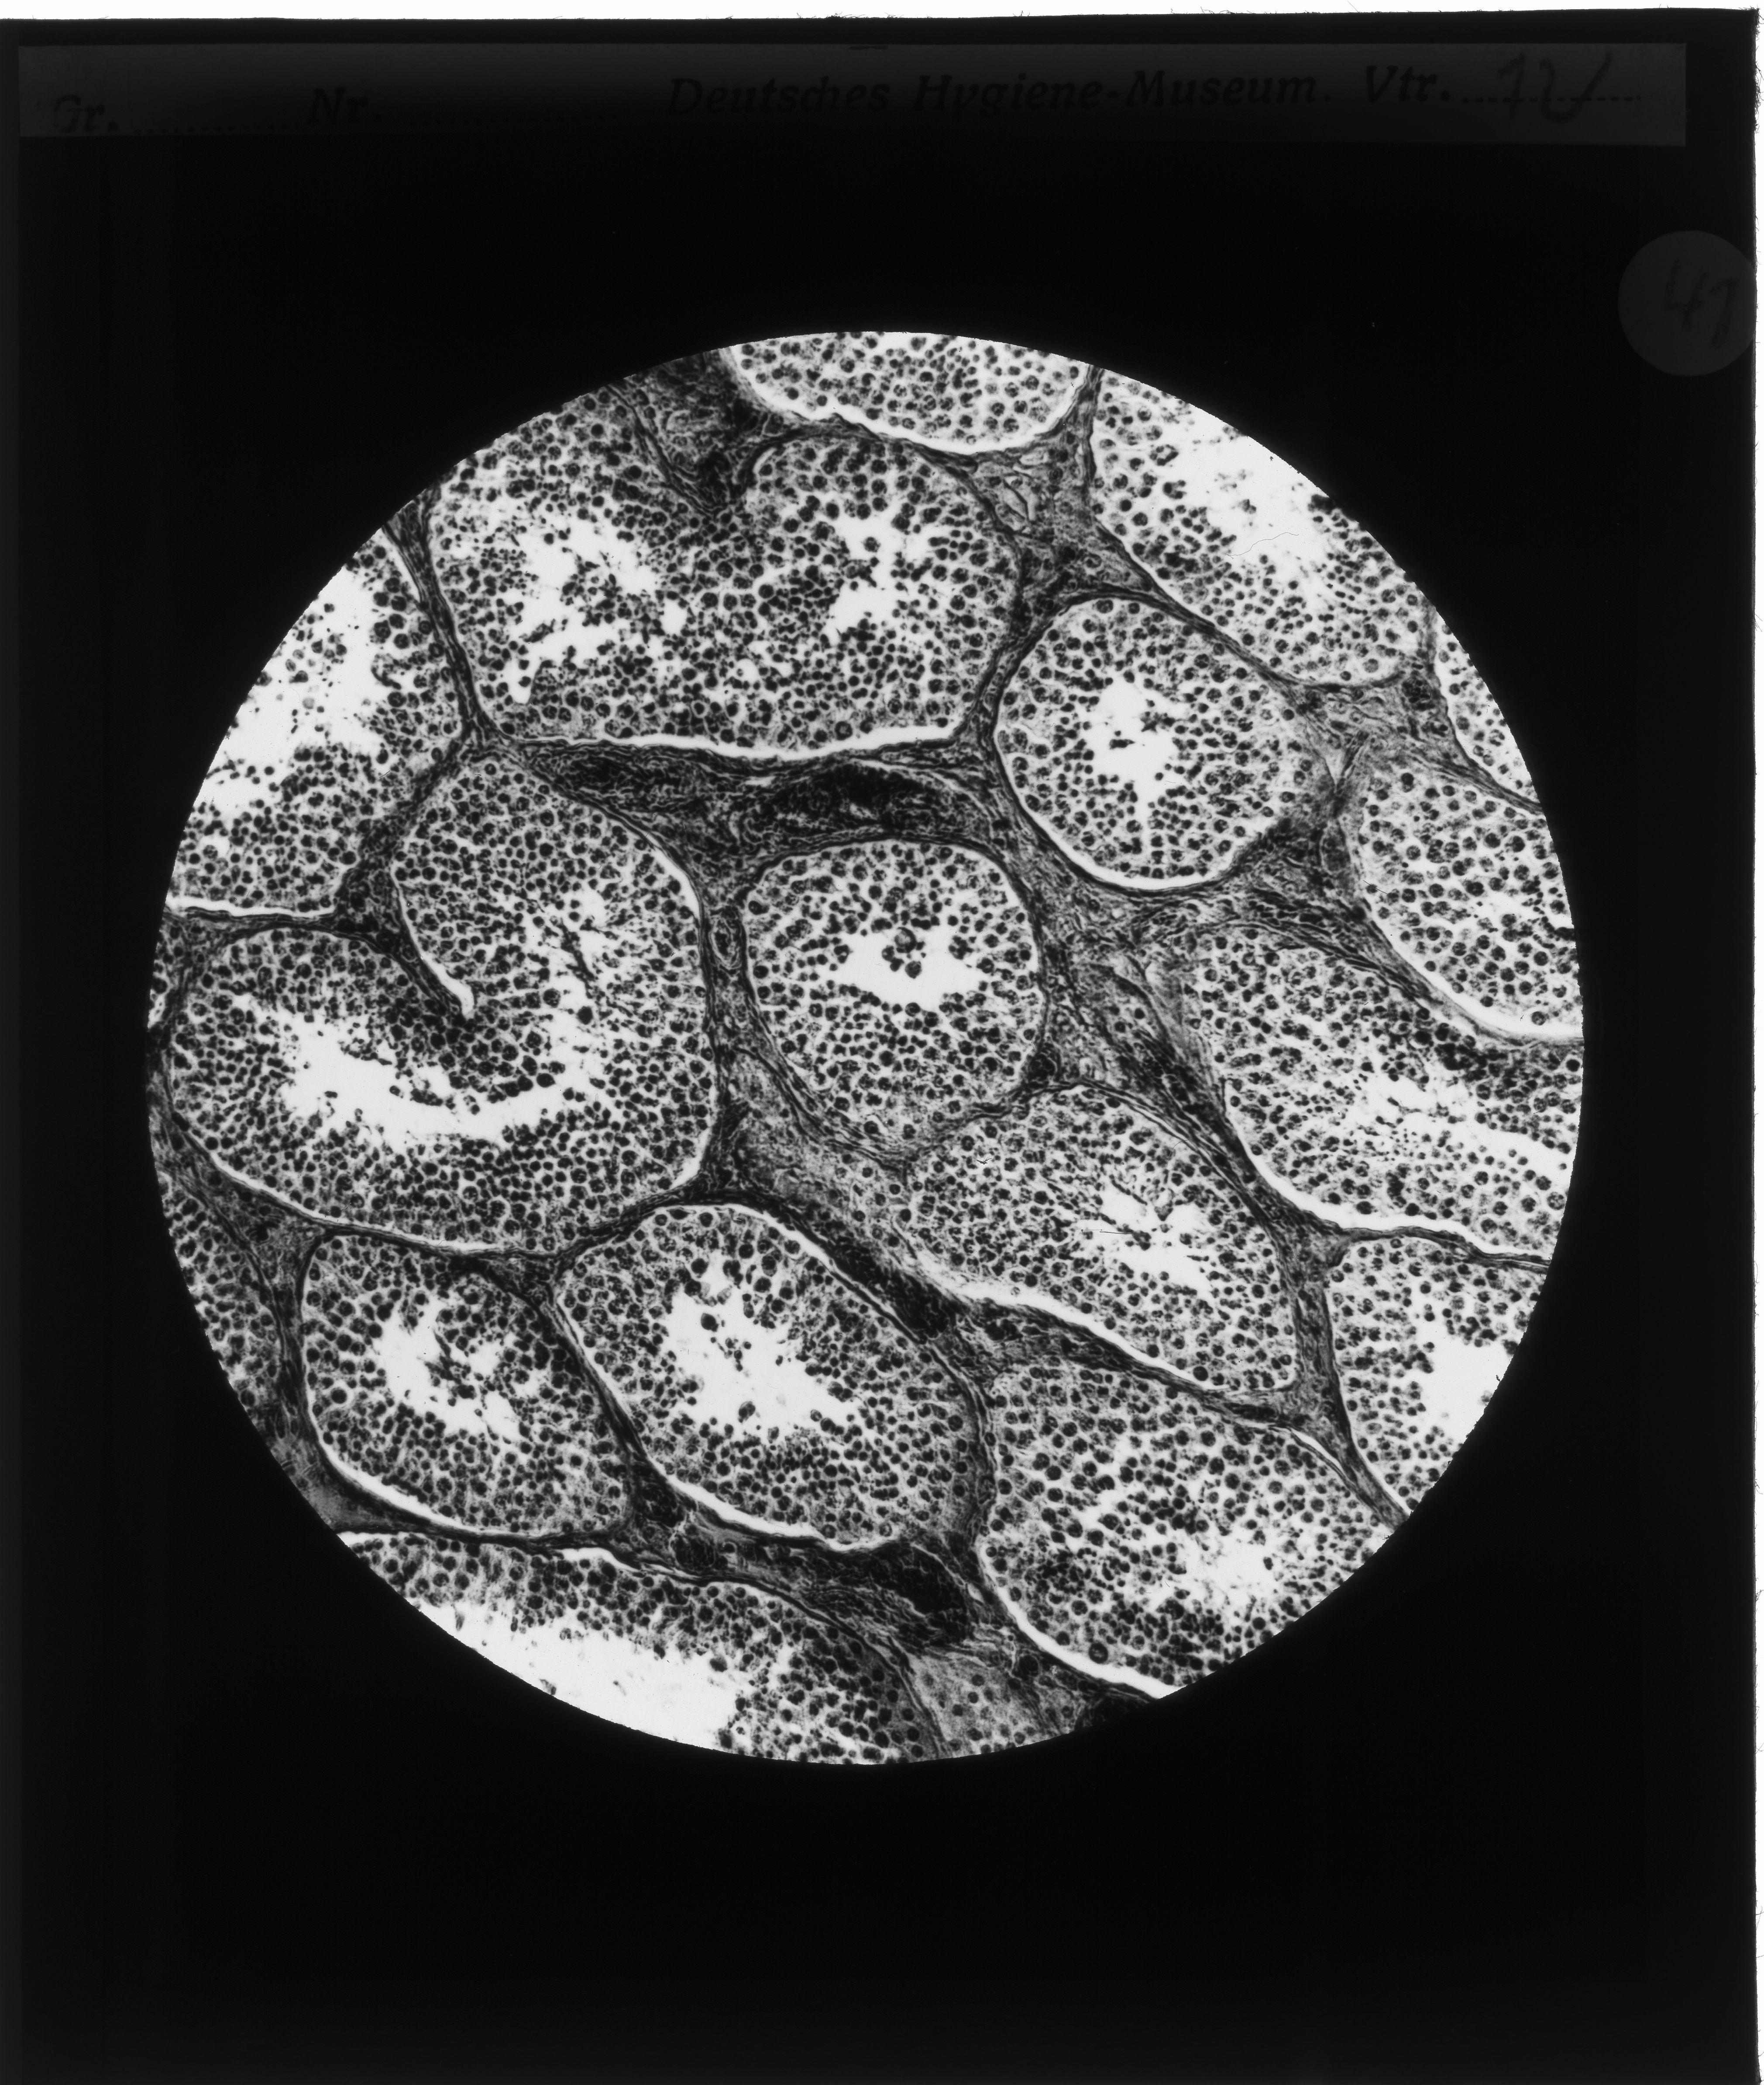

Geschrumpfte Hodenkanälchen, „Degeneration“ und „entartete“ Nachkommenschaft

Gustav von Bunge (1844–1920), Basler Physiologe und ein prominenter Vertreter der wissenschaftlich geführten Abstinenzbewegung, postulierte, ausgehend vom degenerationstheoretischen Gedanken, dass der weit verbreitete Alkoholismus nicht nur den trinkenden Individuen schade, sondern eine Bedrohung der Gesellschaft darstelle, die in einer „Degeneration“ des „Volkes“ münden würde. Man bekämpfte also nicht den individuellen Alkoholismus, sondern die kollektive „Volkskrankheit“. Alkoholiker wurden so als „minderwertige“ Menschen denunziert, die mit ihrem „entarteten“ Erbgut den „Volkskörper“ schwächen. Medizinisch-mikroskopische Darstellungen liefern dafür den Beleg.

Querschnitt durch Hoden

Querschnitt durch Hoden bei einem 20järigen Trinker. (nach einem mikr. Originalpräparat von Prof. Weichselbaum). Keimgewebe entartet, zwischen den geschrumpften Hodenkanälchen massenhaft Bindegewebe.